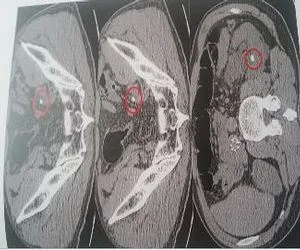

Immagine di calcolo renale

La diagnostica strumentale di 1° Livello è rappresentata dall'ecografia renale e vescicale,la diagnostica strumentale di 2° livello è rappresentata dalla TAC spirale a basso dosaggio e senza mezzo di contrasto. Quest'ultima ci consente di individuare con precisione la presenza di calcoli in tutto l'apparato urinario. Altri esami meno utilizzati sono l'urografia e la pielografia con mezzo di contrasto.